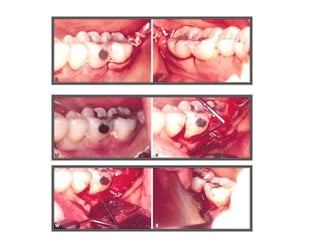

TRATAMENTO DAS LESÕES

ENDOPERIODONTAIS

Hemisseccção

DEL RIO, 1996